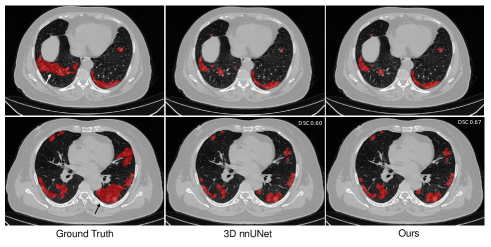

Refer to caption

Figure 3: Visual comparison of COVID-19 infection segmentation by different methods on 3D COVID-19 segmentation benchmark dataset from axial view.

To evaluate the effectiveness of the key components in our framework, we conduct ablation studies by removing the feature relation consistency loss. As shown in Table III, it is observed that all our methods can achieve better performance on all metrics compared with fully supervised methods, showing the effectiveness of our method. Besides, the usage of LrcGsuperscriptsubscript𝐿𝑟𝑐𝐺L_{rc}^{G} and LrcTsuperscriptsubscript𝐿𝑟𝑐𝑇L_{rc}^{T} can both further improve the segmentation performance compared with baseline. When removing the target relation consistency, the average segmentation performance of five folds is degraded by 0.4% and 0.2% on DSC and NSD, respectively. The result proves that the usage of target relation consistency loss LrcTsuperscriptsubscript𝐿𝑟𝑐𝑇L_{rc}^{T} can enforce the target encoder to be more discriminative, so as to improve the segmentation performance. However, the improvement is susceptible to the domain difference. Besides, we also conduct experiments of our backbone by removing the general relation consistency loss LrcGsuperscriptsubscript𝐿𝑟𝑐𝐺L_{rc}^{G}. In this way, the general encoder is frozen and are not updated during the training procedure, which means that the knowledge transfer is not available. The experimental results demonstrate that the average segmentation performance is degraded by 0.6% and 0.3% on DSC and NSD, showing the importance of knowledge transfer in our collaborative learning scheme. Some segmentation results of our method and 3D nnUNet are illustrated in Fig.3 for visual comparison. As shown in the figure, our method can generate segmentation results with more accurate boundaries in Fig.3 (a)(b), and less segmentation mistakes in small infection areas in Fig.3 (c)(d)(e). These results demonstrate that the collaborative learning approach can better exploit shared knowledge from non-COVID cases, leading to better performance when generalizing on test data.